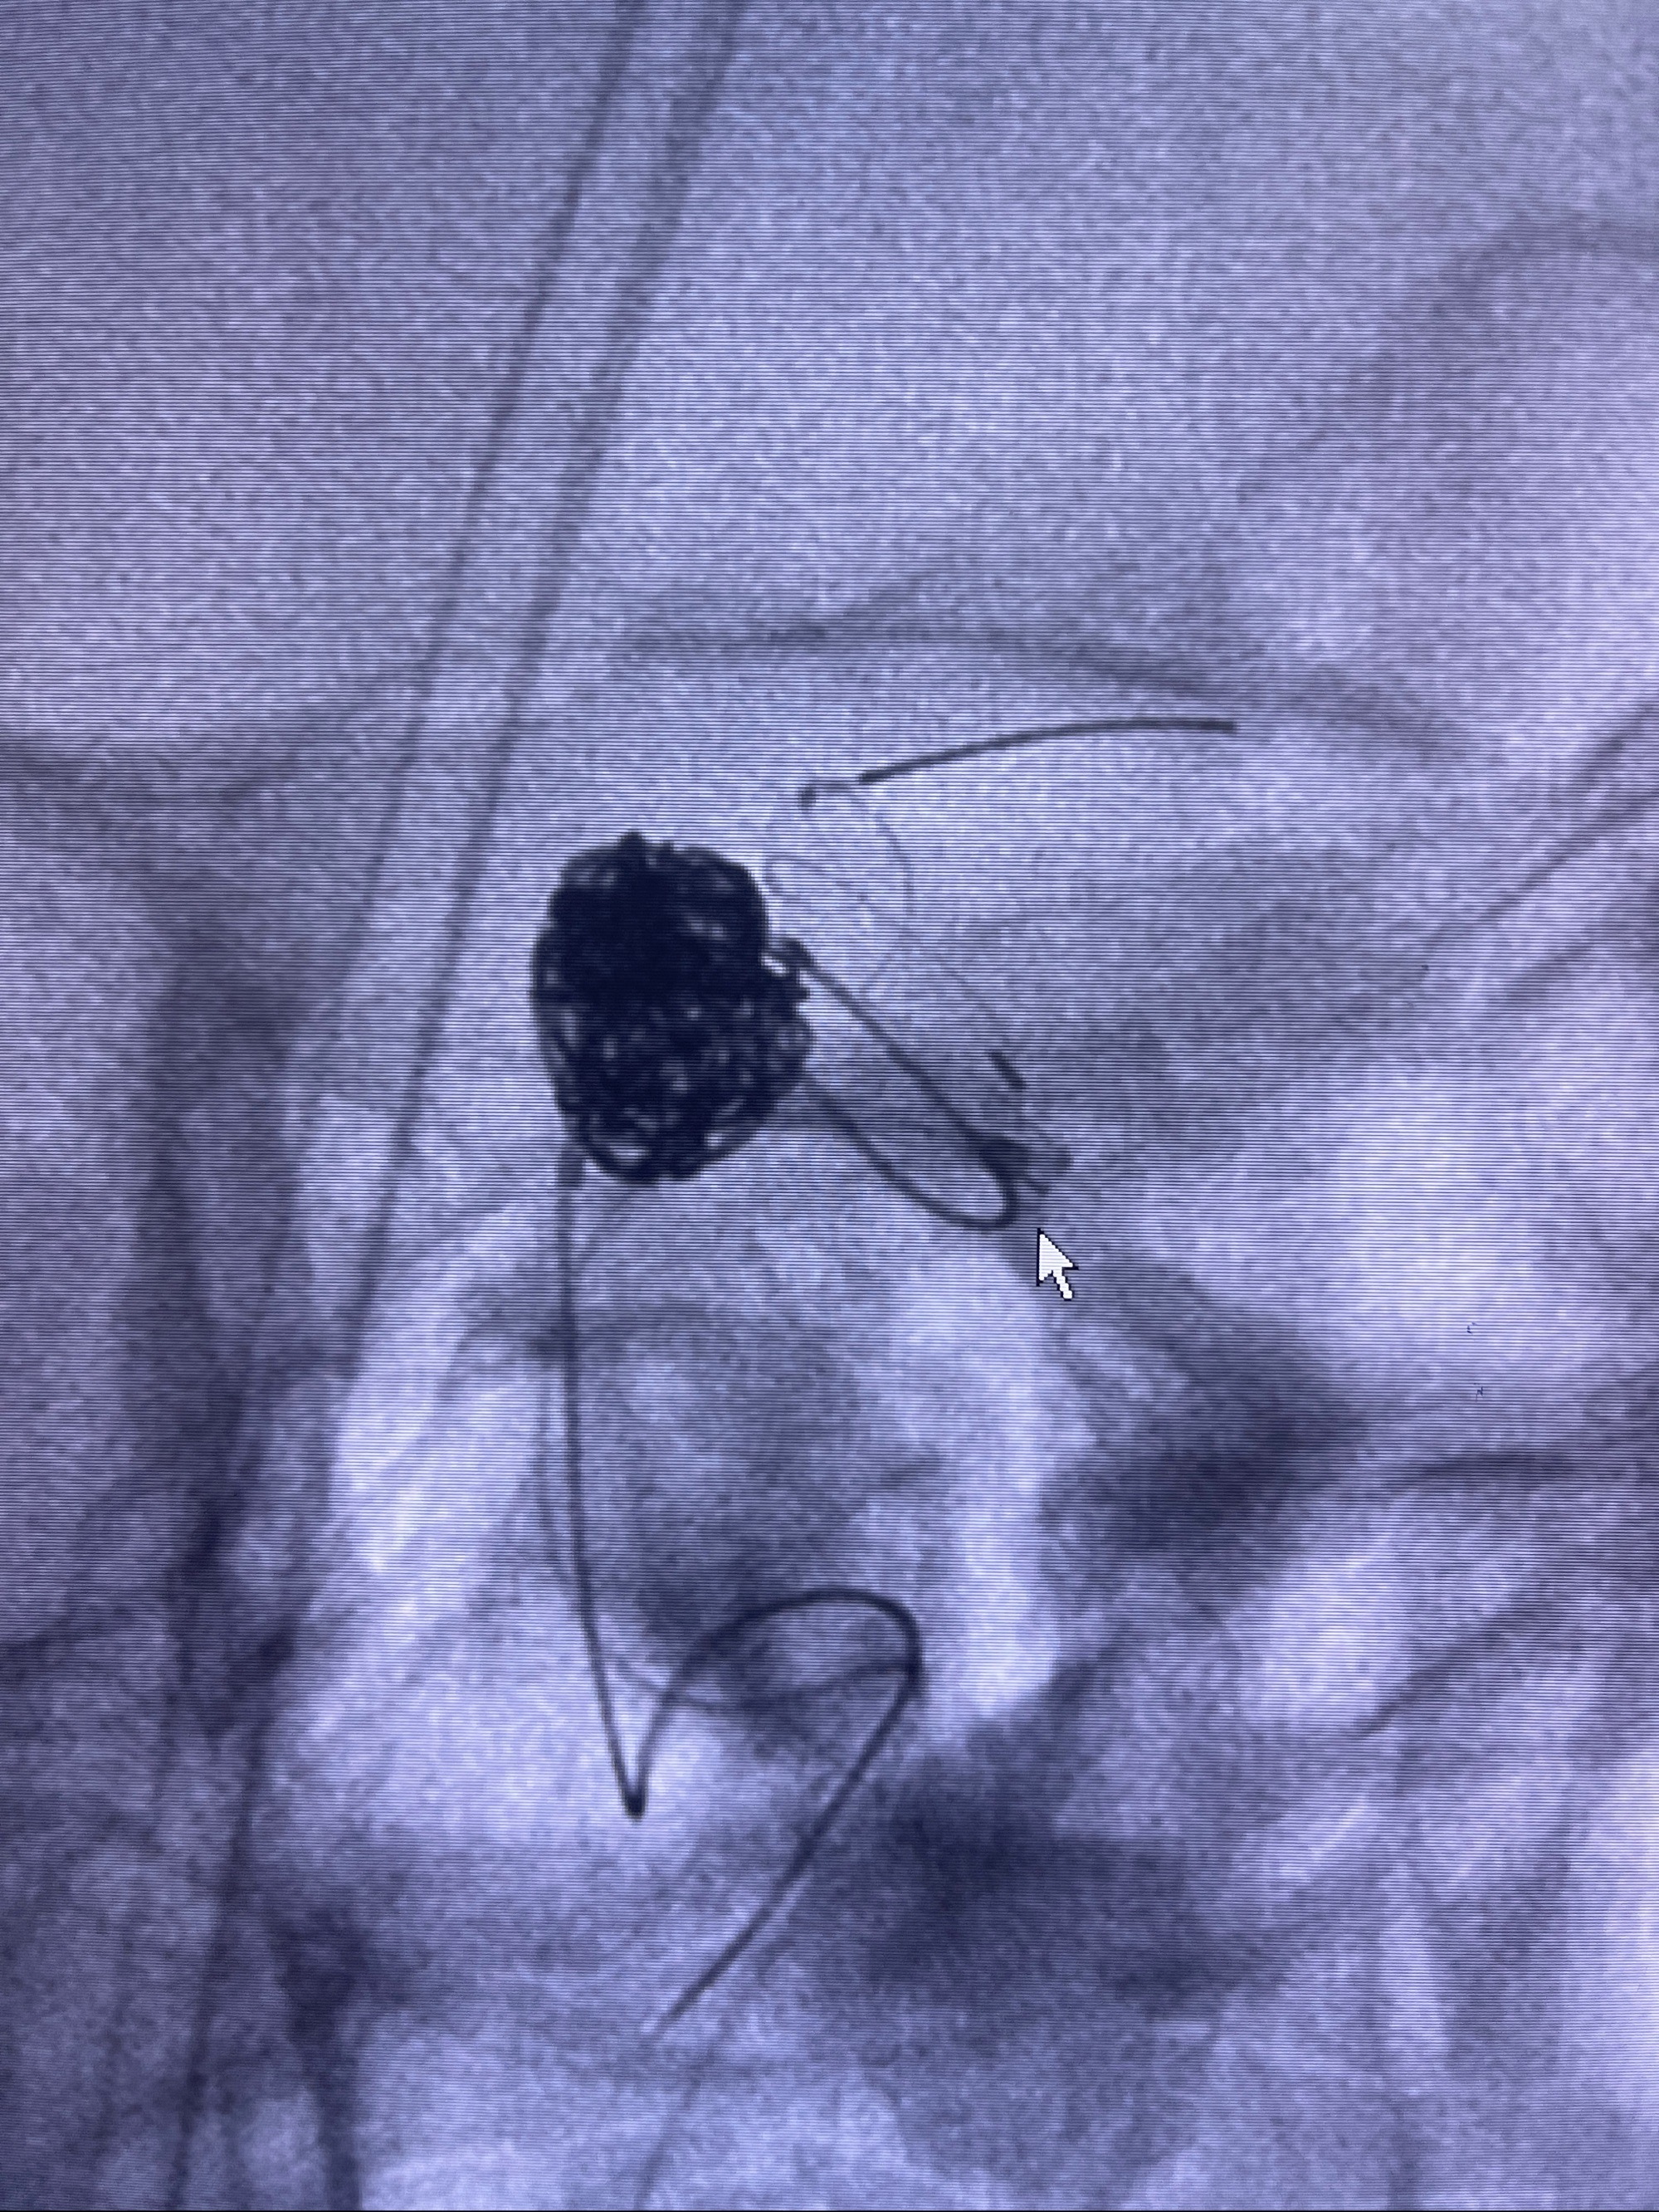

2023-09-06全麻下行左侧颈眼动脉瘤

密网支架辅助栓塞

- Tubridge 4.0-20mm密网支架

- 加奇微弹簧圈:7*30/6*20/5*20/2*8

术后3D显示支架贴壁佳